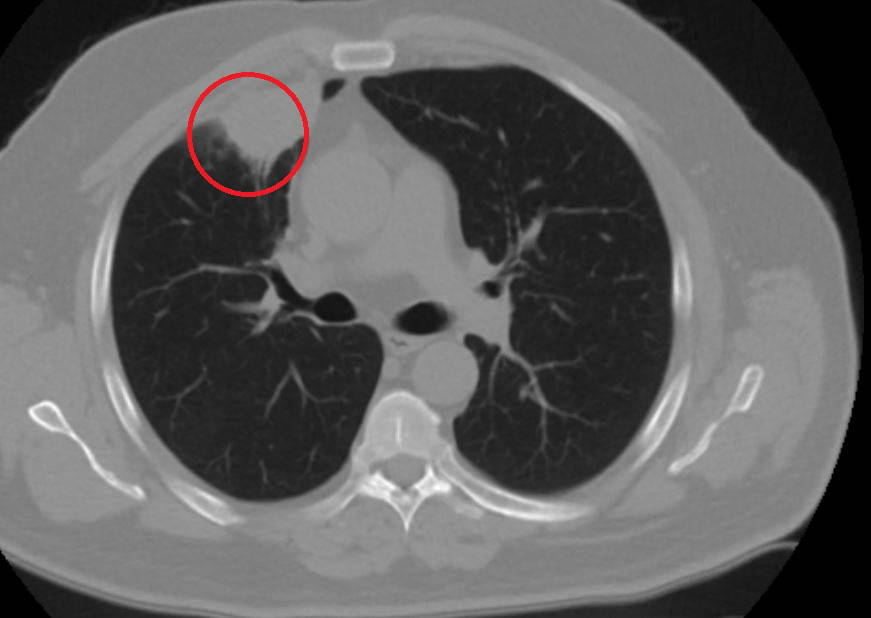

"Hastamız, çalıştığı başka bir kentte göğsünden darbe alıyor ve ağrıları geçmeyince bir üniversite hastanesine başvuruyor. Burada hastaya bir akciğer grafisi çekiliyor. Sağ akciğerinde bir kitleye rastlanıyor. Daha sonra hastaya, bir akciğer tomografisi çekiliyor ve göğüs cerrahisi için önemli büyüklükte olan 4 santimetre çapında, akciğer kanserine benzer özellikte radyolojik bulgular olan bir kitle tespit ediliyor. Daha sonra hastaya yapılan ileri tetkiklerde akciğer kanseri teşhisi konuluyor. Hastaya bir cerrahi planlanıyor. Hasta Kahramanmaraşlı olduğu için kendi memleketine gelmeyi tercih ediyor. Bize başvurdu ve göğüs ağrısı şikayeti vardı. Öksürük, nefes darlığı, balgam çıkarma, ateş gibi şikayetleri yoktu."

"Hastayı biz de değerlendirdik ve ameliyat olmasına karar verdik. Çünkü akciğer kanserine çok benzer radyolojik bulguları vardı. Sağlık Bakanlığımızın kuralları gereği her hastayı ameliyat öncesi PCR testi yapılır. Biz de ameliyat gecesi hastadan PCR testi aldık ve testi pozitif geldi. Ameliyatımızı 14 gün erteledik ve hastamıza koronavirüs tedavisi uygulandı. Hasta 14'üncü gün tekrar bize başvurdu ve yapılan PCR testi negatif çıktı. Yeni bir tomografi çektik ve tümörün tamamen ortadan kalktığını gördük. Şimdi sonuç bilgilerinden başlangıca gittiğimizde, bu bir akciğer kanseri olsaydı, ortadan kalkması mümkün değildi. Başka bir patolojiye bağlı durum olsaydı, yine verdiğimiz tedaviyle ortadan kalkmasını çok beklemeyiz. Antiviral tedavisi verdik ve hastanın radyolojik bulguları neredeyse tamamen normale döndü. Hastaya bunu izah ettik, 'Dünya literatüründe hiç görülmeyen bir radyolojik bulgu' diyerek. Bu gördüğümüz manzara artık hastanın akciğer grafisinde yok, akciğer kanseri değil. "